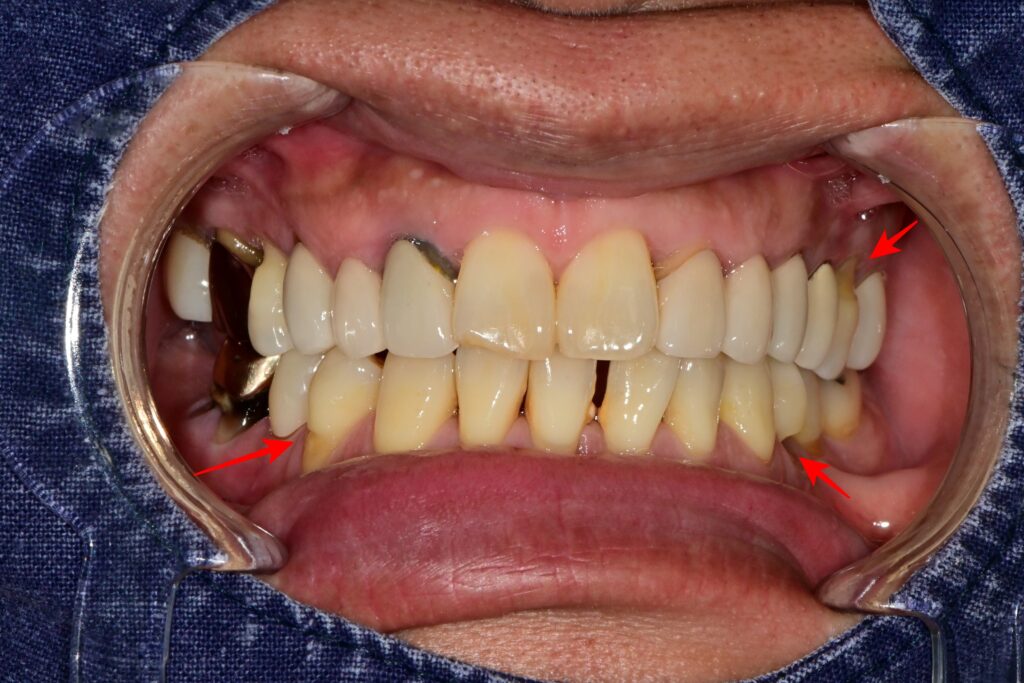

검진 과정에서 오른쪽 아래의 오래된 크라운에도 문제가 발견되었습니다. 크라운에 구멍이 나 있었고, 그 속으로 이차우식이 진행된 상태였습니다.

특히 이 치아는 잇몸이 내려가면서 치아 뿌리가 드러났고, 잇몸 경계 부위가 패여 있는 치경부마모증까지 겹쳐 있었습니다.

많은 분들이 “오래된 크라운은 무조건 교체해야 하나요?”라고 묻습니다. 정답은 **”그렇지 않습니다”**입니다. 하지만 이번 케이스처럼 마진(Margin)이 들뜨거나, 내부에 충치가 있거나, 구멍이 난 경우에는 교체가 필요합니다.